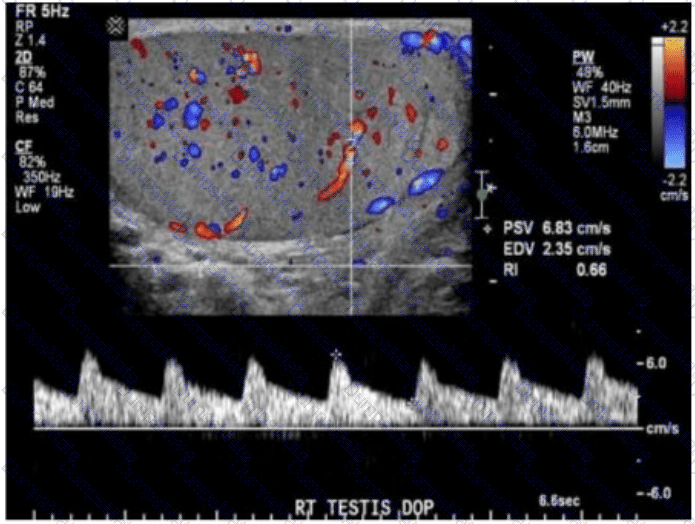

Which diagnosis is most consistent with this image from a patient with acute scrotal pain?

AB-Abdomen Question 33

Options:

A.

Scrotal abscess

B.

Testicular rupture

C.

Testicular torsion

D.

Epididymitis

Buy Now